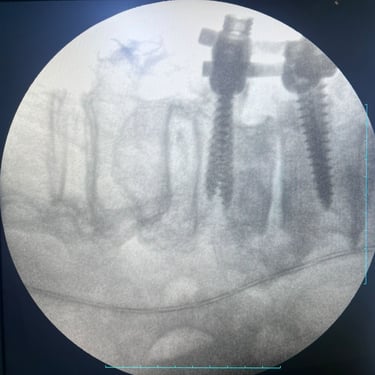

🧠 Hernia Lumbar Sintomática: Estabilidad y Descompresión con Artrodesis y TLIF.

La hernia lumbar sintomática causa dolor lumbar y radicular persistente. La artrodesis con tornillos transpediculares y TLIF es una opción quirúrgica eficaz para descomprimir las raíces nerviosas, estabilizar la columna y mejorar la calidad de vida del paciente.